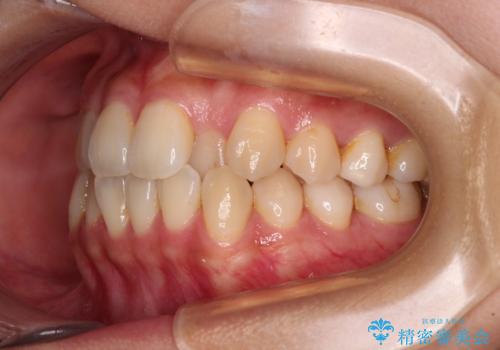

左下の奥歯は根管治療後に放置されていたため、咬み合わせを調整しながら矯正治療を行い、最後にオールセラミッククラウンにて補綴治療を行うこととしました。

舌のトレーニングをしっかりと行っていただき、補綴治療も含めて1年強の短期間で治療を終えることができました。